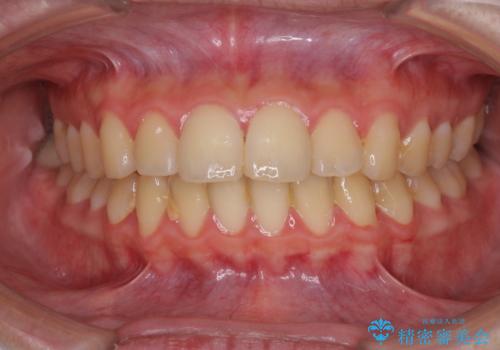

口元が出てるの気になる、引っ込めたい ワイヤーによる抜歯矯正で横顔の改善

- 口元が出てるのが気になるとのことで来院されました。

歯のがたつきはあまりなかったのですが、口唇が閉じずらく、口元の突出感が確認できました。

上下左右の歯を1本ずつ抜歯して、そのスペースを利用して口元を引っ込める計画としました。

口元を下げて口唇を閉じやすくする場合、抜歯矯正をお勧めさせていただくことが多いです。